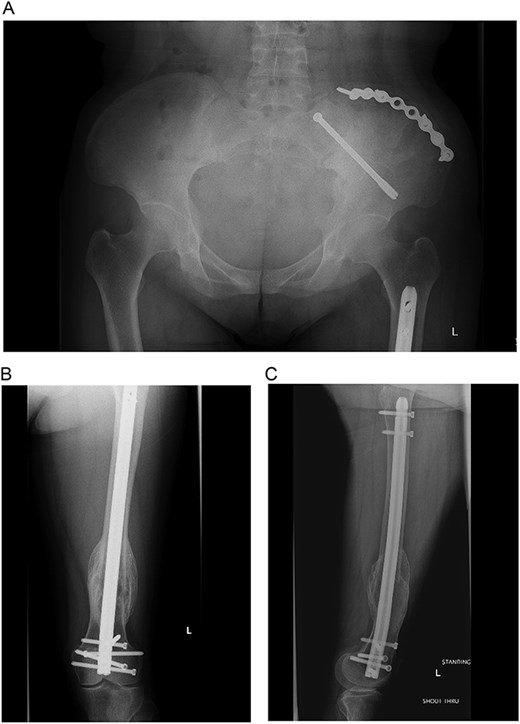

At the time of pelvic fixation, a bone biopsy confirmed the diagnosis of a brown tumor. The patient underwent routine follow-up and was referred to endocrinology for ongoing calcium and vitamin D deficiency management. At over one year post-op, she had satisfactory clinical and radiographic healing with stable fixation (Fig. 5A–C). A skeletal survey identified additional resolving brown tumors in the right proximal humerus, left distal humerus, and bilateral tibia. By her last follow-up, all lesions had resolved, and she was discharged from orthopedic trauma and oncology care.

(A–C) Final radiographs showing complete healing >1 year postoperatively.